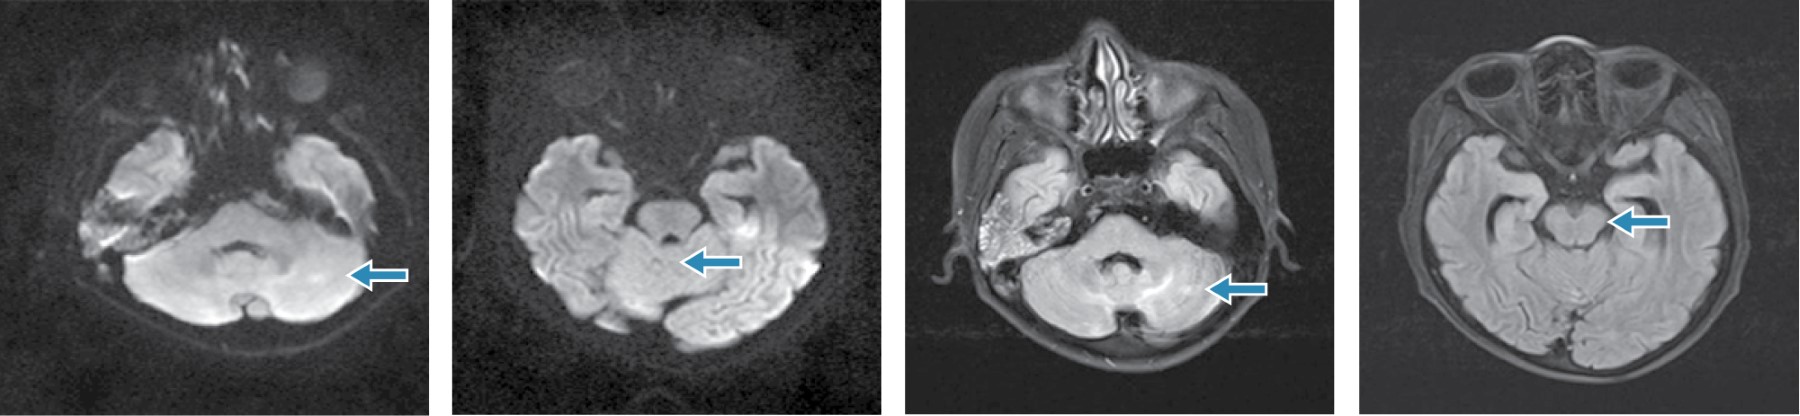

Dentro de los estudios de laboratorio en su abordaje diagnóstico se encontraron leucocitos de 7.9 × 109/L, neutrófilos absolutos 7.1 × 109/L, linfocitos absolutos 0.4 × 109/L, monocitos absolutos 0.5 × 109/L, glucosa 97 mg/dL, creatinina 0.3 mg/dL, sodio sérico 130 mmol/L, potasio 3.7 mmol/L, cloro 88 mmol/L, proteína C reactiva 4.6 mg/dL, procalcitonina 3.2 ng/dL, enzimas hepáticas normales, urocultivo y hemocultivos sin desarrollo. Reporte del líquido cefalorraquídeo: microproteínas 38 mg/dL, lactato deshidrogenasa 12 UI/L, cloro 116 mmol/L, aspecto agua de roca, sin celularidad, panel de encefalitis FilmArray® PCR múltiple negativo, anticuerpos contra M. pneumoniae IgG negativo e IgM positivo, tinta china, tinción Gram, tinción bacterias ácido-alcohol resistentes (BAAR) y cultivos negativos, estudio histopatológico sin infiltración neoplásica. Resonancia magnética (RMN) simple y contrastada de cráneo, con hiperintensidad difusa en secuencia T2 y FLAIR en hemisferio cerebeloso superior e inferior, bilateral, de predominio central y fóveas, con extensión a pedículos cerebelosos posteriores y mesencefálicos; a la administración de contraste se encontró realce de trayecto del nervio óptico en su porción intracraneal, de predominio derecho. Con lo anterior se integran datos de síndrome de PRES asociado a infección por M. pneumoniae, motivo por el cual se indica tratamiento dirigido con levofloxacino a 10 mg/kg/día. Durante la evolución clínica, el paciente no presentó nuevos eventos convulsivos, las cifras tensionales permanecieron normales, no presentó datos de focalización y no se agregaron otros síntomas. A los 13 días, se realiza una nueva RMN de control, donde se observa disminución de la intensidad a nivel de fosa posterior, en relación a estudio previo, sin evidencia de reforzamientos anormales intra- ni extraaxiales que sugieran implantes y neuroeje sin reforzamientos anormormales; angioresonancia normal.

En el síndrome de PRES, la hipertensión arterial se explica de manera hipotética por una perfusión cerebral deficiente, que conlleva a una lesión endotelial mediada por toxinas sistémicas; los factores de riesgo para este síndrome son insuficiencia renal, síndrome nefrótico, nefritis aguda, síndrome hemolítico urémico, dosis altas de esteroides, enfermedades oncológicas y uso de inmunosupresores.8 Sin embargo, en algunos casos, la afección a nivel del sistema nervioso central, puede simular un efecto de masa, simulando neoplasias a este nivel.9 Otros datos que pueden apoyar el diagnóstico son la hipomagnesemia y la afección tradicional en neuroimagen de los lóbulos parietooccipitales, aunque ocasionalmente se observan otras áreas.10 Es importante recordar que a pesar de que las crisis convulsivas son de los datos clínicos más frecuentes, éstas pueden variar en intensidad y características, pudiendo observarse crisis epilépticas no convulsivas con focalización secundaria o de gran mal. La resolución de los hallazgos por RNM es espontánea, en ocho días aproximadamente, por lo que el tratamiento específico es muy importante para delimitar estas lesiones.7,11 El diagnóstico serológico de afección de sistema nervioso central por M. pneumoniae es controversial; habitualmente, los anticuerpos IgM aparecen durante la primera semana de la infección y preceden por dos semanas a los anticuerpos IgG; la detección de IgM positiva en suero en correlación con la clínica compatible sería suficiente para definir la primoinfección por M. pneumoniae, otros autores consideran que para definir la infección del sistema nervioso central se requiere, además de la clínica, detección de IgM positiva en suero y el aumento significativo de títulos de IgG analizados en muestras pareadas, o bien, por detección de PCR positiva en el líquido cefalorraquídeo (LCR) en forma aislada, aunque es infrecuente su hallazgo; por lo que es importante considerar que esta entidad es un reto diagnóstico.12 En el contexto de este paciente, debido a sus manifestaciones clínicas, se abordó de manera inicial para descartar los diagnósticos más frecuentes. Sin embargo, al tener una enfermedad oncológica subyacente, es importante considerar otras posibilidades diagnósticas de forma integral, con lo que se incrementa el pronóstico a corto plazo en este tipo de pacientes (Figuras 1 y 2).